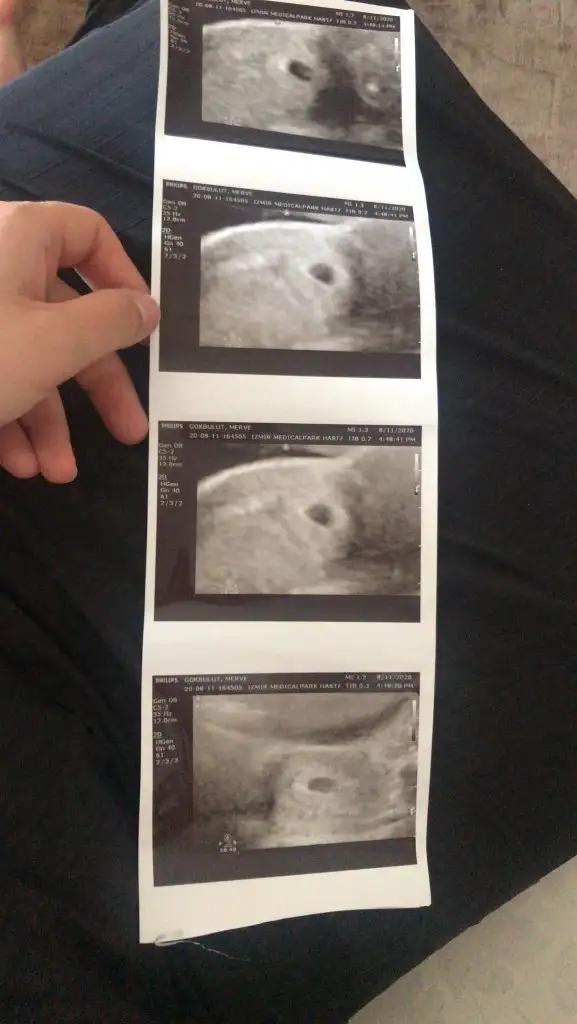

Devlet hastanesine randevu alıp bu kağıdı verip yaptırabilir ya da sağlık ocağında aile hekimine gidebilirsin canımKızlar selam çok şükür bugün keseciği görebildikkalp atışı için henüz erkenmiş daha 5.5hafta filan dedi dr umuz herşey normal görünüyor inş öyle devam eder

Eki Görüntüle 2674047 Eki Görüntüle 2674050